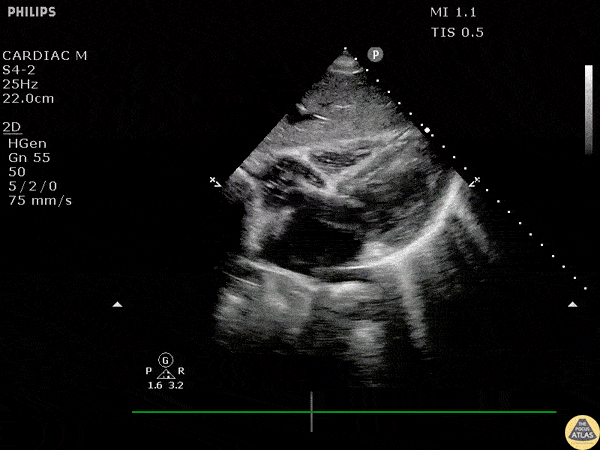

This ultrasonographic finding, first described in the 1990s, can be seen in both severe tricuspid regurgitation and cardiac tamponade. It refers to abnormal diastolic movement of this structure due to elevated right-sided pressures and may be missed unless you freeze-frame during ventricular diastole.

What is RV trampolining of the lateral wall and or intra-ventricular septum.